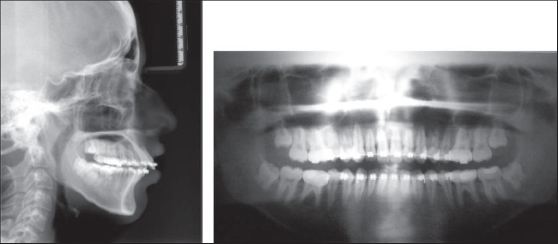

a. The skeletal stability for both Group I [Figures 35] and Group II [Figures 68] was measured at three different periods; preoperative (T1), 1-week postoperative(T2), and 6-month postoperative (T3) using a lateral cephalogram and analyzed using cephalometric analysis. The cephalometric analysis was carried out considering the following points[4] [Figure 9].

Figure 3: Preoperative lateral cephalogram and orthopantamogram-group I

thumb

Figure 4: 1-week postoperative lateral cephalogram and orthopantamogram- Group I

Figure 5: 6-month postoperative lateral cephalogram and orthopantamogram- Group I